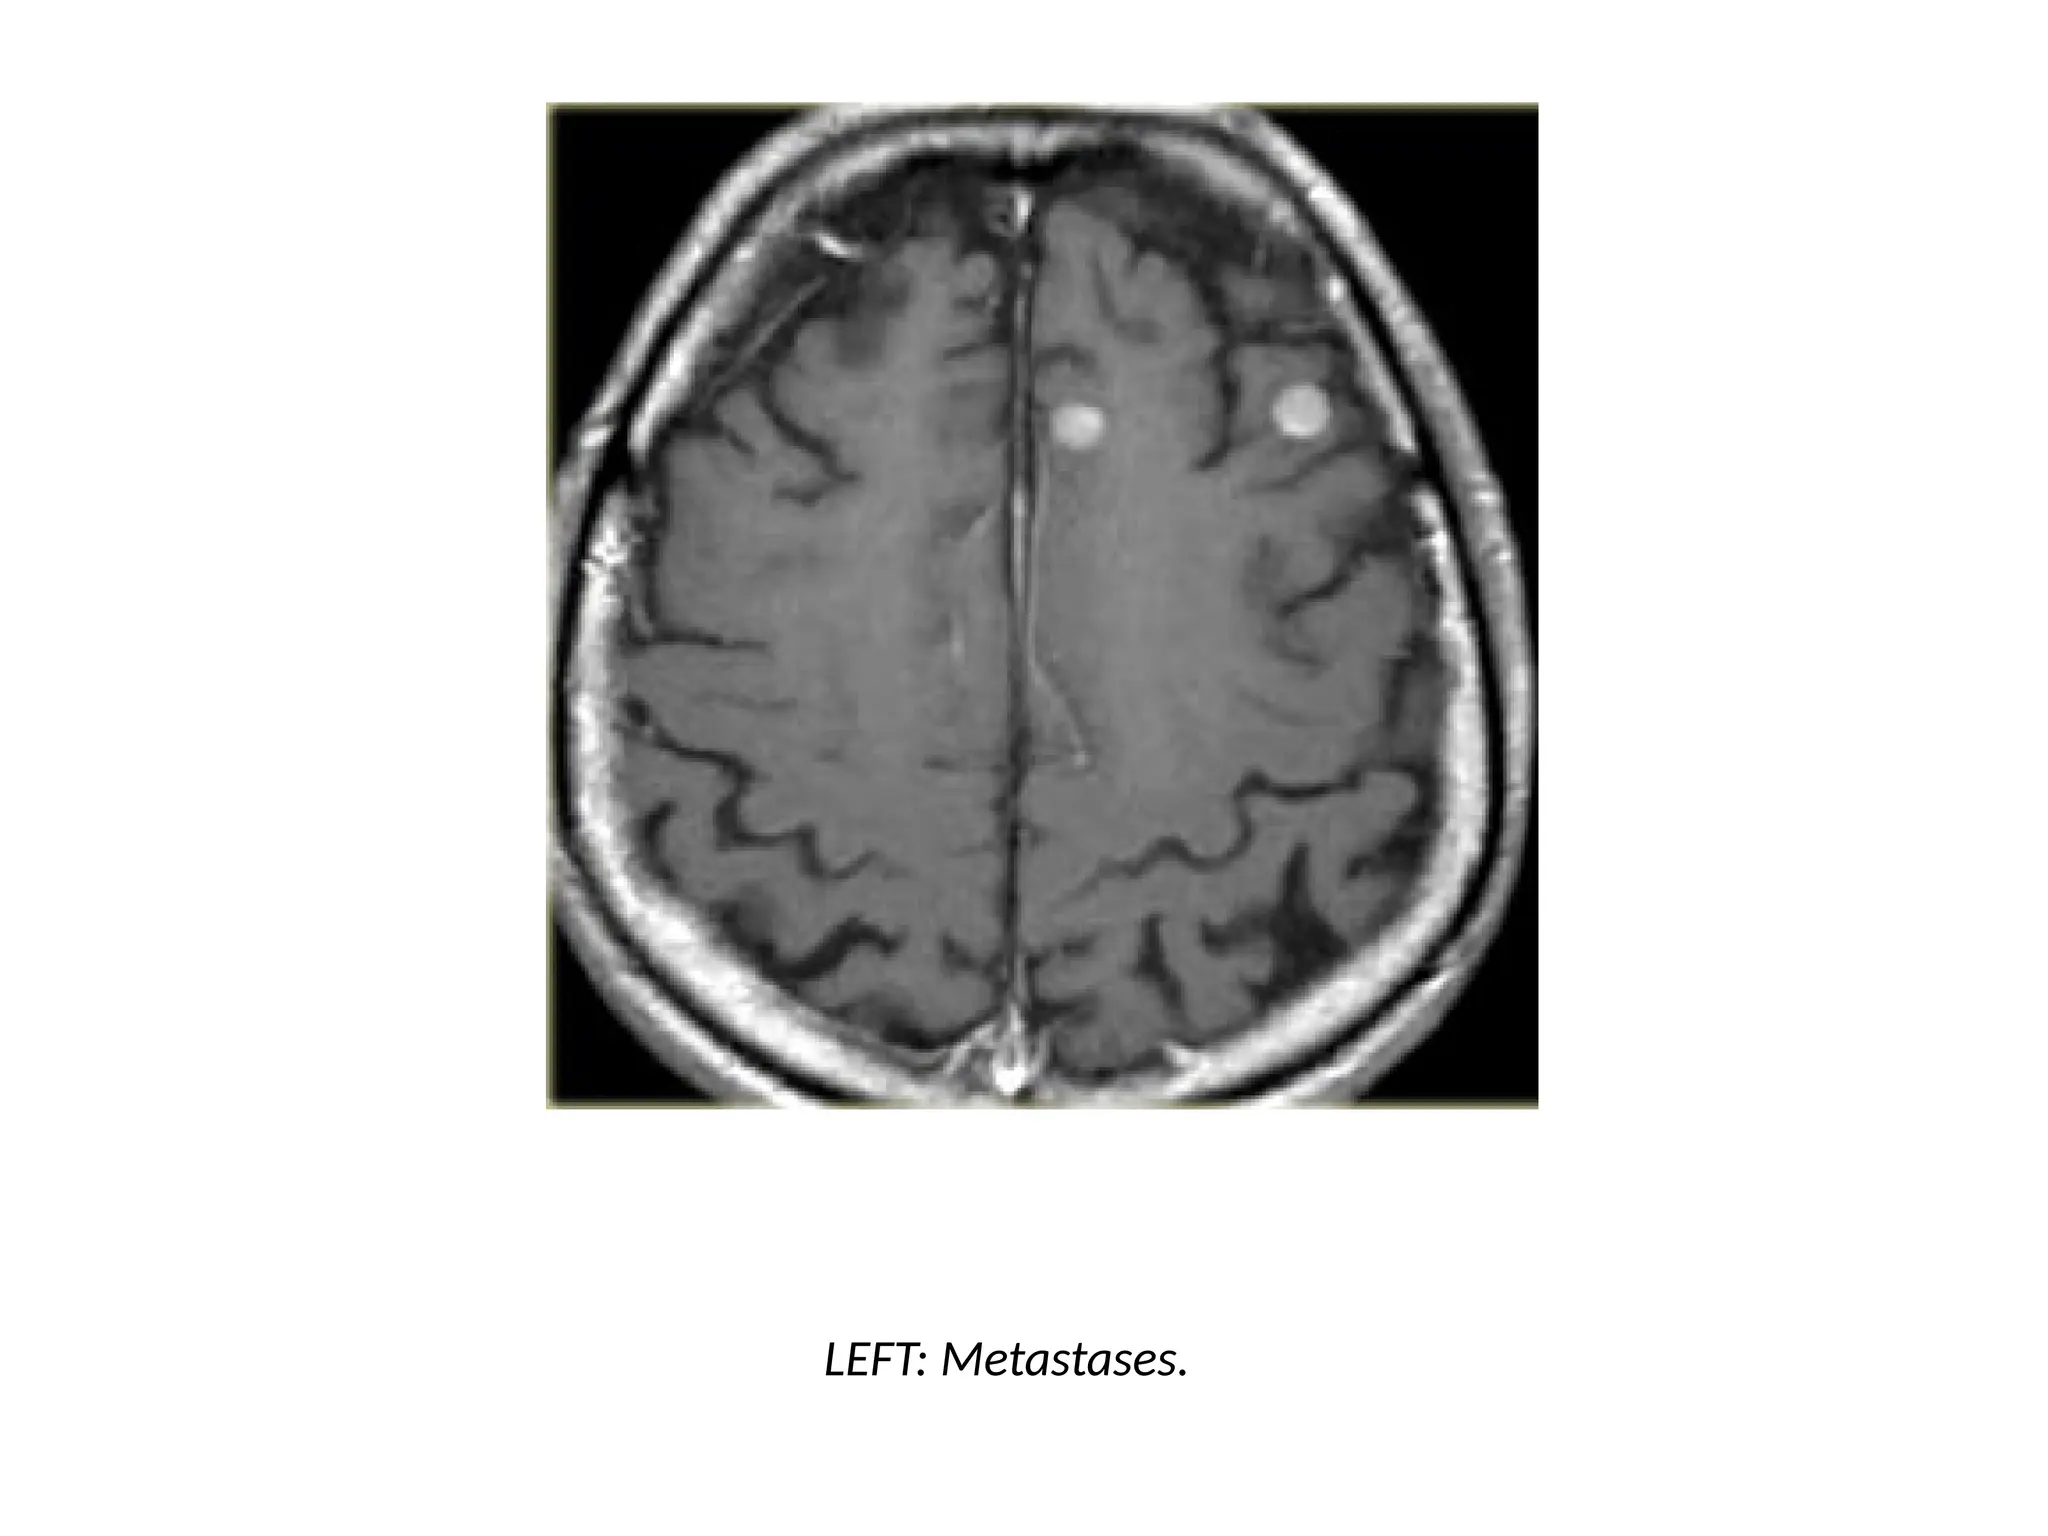

Multifocal disease

• Multiple tumors in the brain usually indicate metastatic disease.

• Primary brain tumors are typically seen in a single region, but

some brain tumors like lymphomas, multicentric glioblastomas

and gliomatosis cerebri can be multifocal.

• Some tumors can be multifocal as a result of seeding metastases:

this can occur in medulloblastomas (PNET-MB), ependymoma,

GBM and oligodendrogliomas.

• Meningiomas and Schwannomas can be multiple, especially in

neurofibromatosis type II.

LEFT: Metastases.